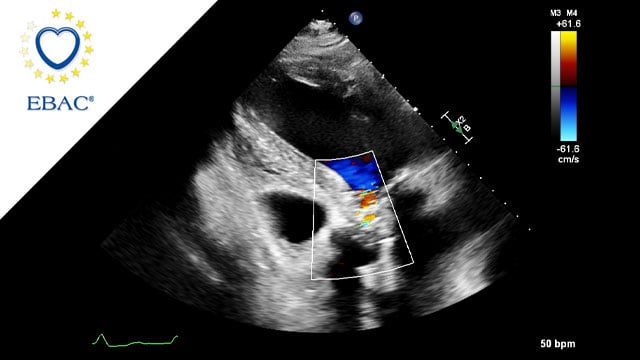

Severe MR in a high-risk patient with a suboptimal anatomy for M-TEER: what other options can we find?

Multimodality imaging reveals fibro-calcific leaflet disease, restricted motion, and a short posterior leaflet, making him a suboptimal candidate for M-TEER and prompting consideration of transcatheter mitral valve replacement. How would you treat?